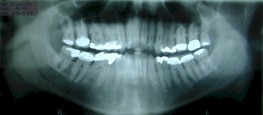

Electrogalvanismo por

presencia de amalgamas en el maxilar superior e inferior

saneamiento de la boca. Al observar la radiografía y al examen clínico nos

llamó la atención la variedad de metales y la presencia de cordales en una

|

Rx en la que se observa metales en boca |

Este paciente tenía problemas de electrogalvanismo entre

los diferentes metales en boca |

DESPUES

Se le retiró las cordale y todas las amalgamas quedando solo una variedad

de metal que es el cromoniquel evitando de este modo el electrogalvanismo |